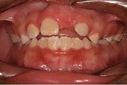

Diş ekimi, kaybedilen dişlerin yerine yapay dişlerin yerleştirilmesi işlemidir. Bu işlem, hem estetik hem de fonksiyonel açıdan birçok avantaj sunmaktadır. Diş ekimi, günümüzde diş hekimliği alanında en yaygın kullanılan yöntemlerden biri haline gelmiştir. Bu makalede, diş ekiminin faydaları detaylı bir şekilde ele alınacaktır. Diş Ekimi Nedir?Diş ekimi, kaybedilen dişlerin yerine cerrahi bir işlemle titanyum veya benzeri malzemelerden yapılan yapay diş köklerinin yerleştirilmesini içeren bir tedavi yöntemidir. Bu işlem, diş kaybının neden olduğu estetik kaygıları gidermenin yanı sıra, çiğneme fonksiyonunu da yeniden kazandırmaktadır. Diş Ekiminin Estetik FaydalarıDiş ekimi, hastaların gülümseme estetiğini önemli ölçüde iyileştirmektedir. Aşağıdaki avantajlar estetik açıdan dikkate değerdir:

Diş Ekiminin Fonksiyonel FaydalarıDiş ekiminin fonksiyonel avantajları da oldukça önemlidir. Bu avantajlar şunlardır: